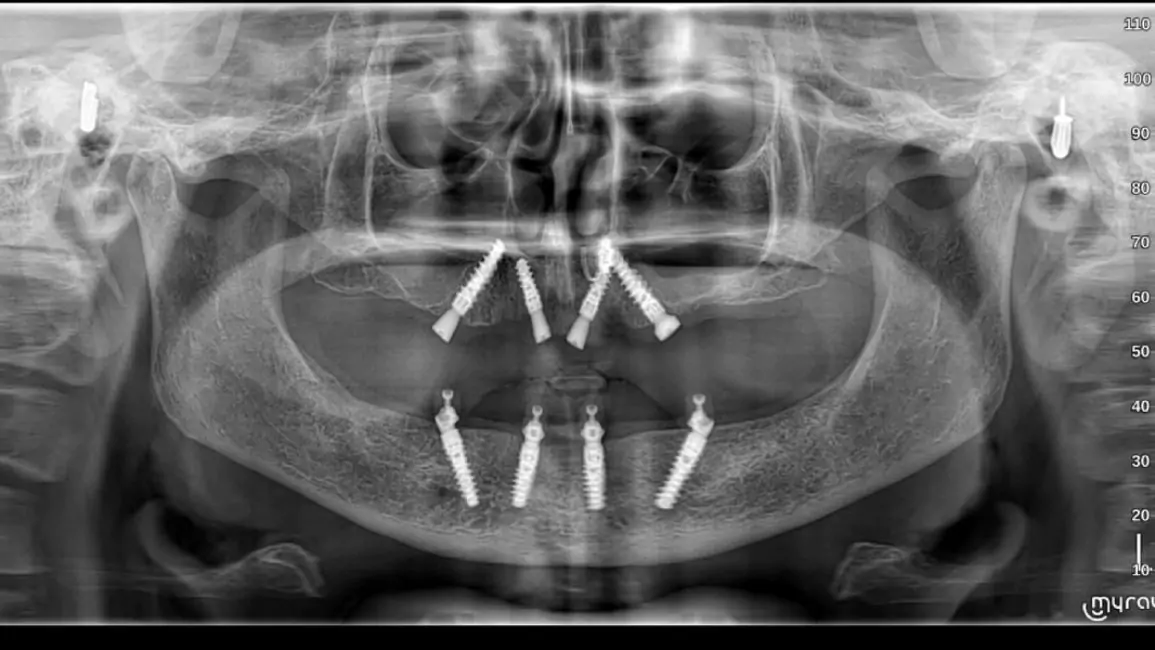

All-on-4 Implants

It is a revolutionary concept in which only four implants support an entire arch of teeth. It is minimally invasive and cost-effective.